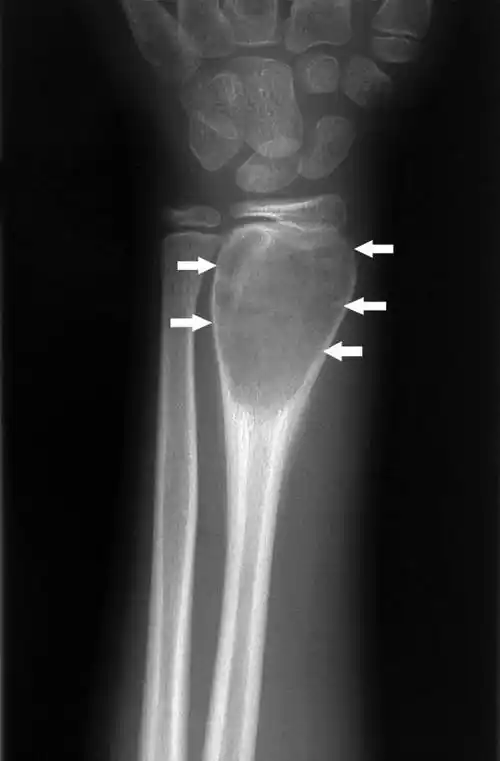

腕部动脉瘤性骨囊肿